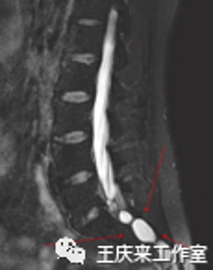

临床中,“尾骨痛”的诊断主要依靠病史和体格检查。患者以骶尾部疼痛为主要表现,并通常在坐姿不正确或坐姿站起时明显,按压或触及尾骨局部出现疼痛。直肠指检检查对于本病的诊断具有重要意义,可用于判断局部组织压力敏感反应、尾骨活动度等情况。注意必要时须完善影像学检查如CT、磁共振等以鉴别诊断。